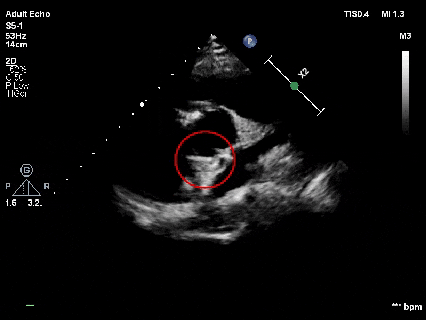

释放前超声

释放前超声下封堵器型态良好,骑跨室间隔两侧

释放封堵器

释放后超声

超声下可见室水平和房水平都无残余分流

心脏彩超:心脏超声下可见两个封堵器双盘稳固夹持,无残余分流;

术后1个月心脏超声,房室水平皆无残余分流